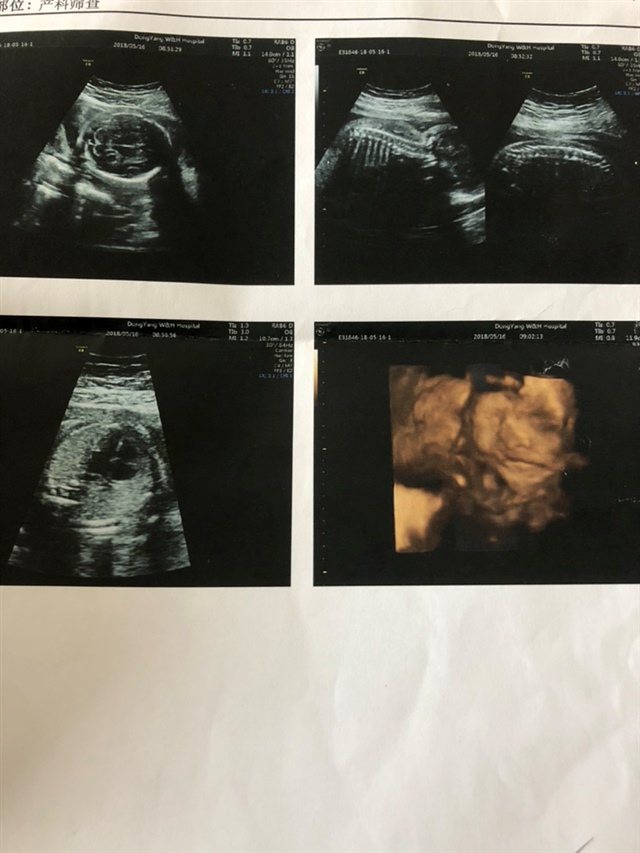

孕37周+2天

孕30周+0天